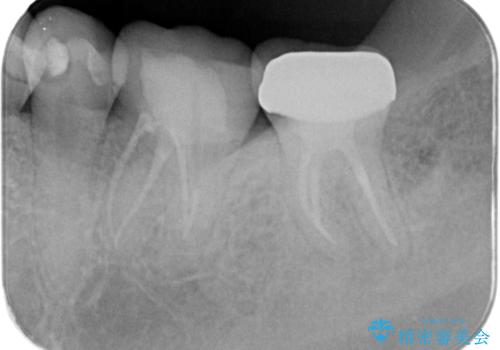

レントゲンや口腔内所見にて以下のような説明ののち、患者様が保存を希望されたため、当院では根管治療~オールセラミッククラウンにて修復処置を行いました。痛みも消えて、経過良好です。

病気の原因は細菌であるため、細菌数を減らすための処置として一般的に②根管治療という選択肢がある。再根管治療の場合は病気が治るのは7割ぐらいであり、それでも治らない場合は意図的再植術を行い9割近くまで成功率を高めることができる。ただし、今回のケースでは根尖が湾曲しているため意図的再植時の破折リスクが高いため適応は難しい。また、根尖の病変が治ったとしても、歯周病、カリエス、脱離や破折リスクがあり治療後抜歯になる可能性もある。治らない可能性や治療したとしても抜歯になる可能性があることを考慮し、③抜歯の選択肢をとる場合もある。

それまでにかかった金額や来院回数、時間、身体的負担などのコスト(費用)に対し、どのぐらいの期間保存できる(効果)かを費用対効果と呼ぶ。例えば、30万円の治療をした歯が、30年保存できることもあれば、1年で割れて抜歯になってしまうこともある。患者さんの治療に対する効果の期待値が10年だった場合、30年保存できれば費用対効果を悪く感じない結果だが、1年しか保存できなければ、費用対効果を悪く感じる結果となる。

であるならば、抜歯してインプラントも悪い選択肢とは言えないが、インプラント治療も同様に一生保存できると確約はできない。そのため、自分が患者の立場であるならば、少しでも長く自分の歯を保存し、最後の手段でインプラントを行う。そのためにできるだけのことをする。費用対効果が悪く感じるリスクがあったとしても、自分の歯を保存する価値は高いと考える。